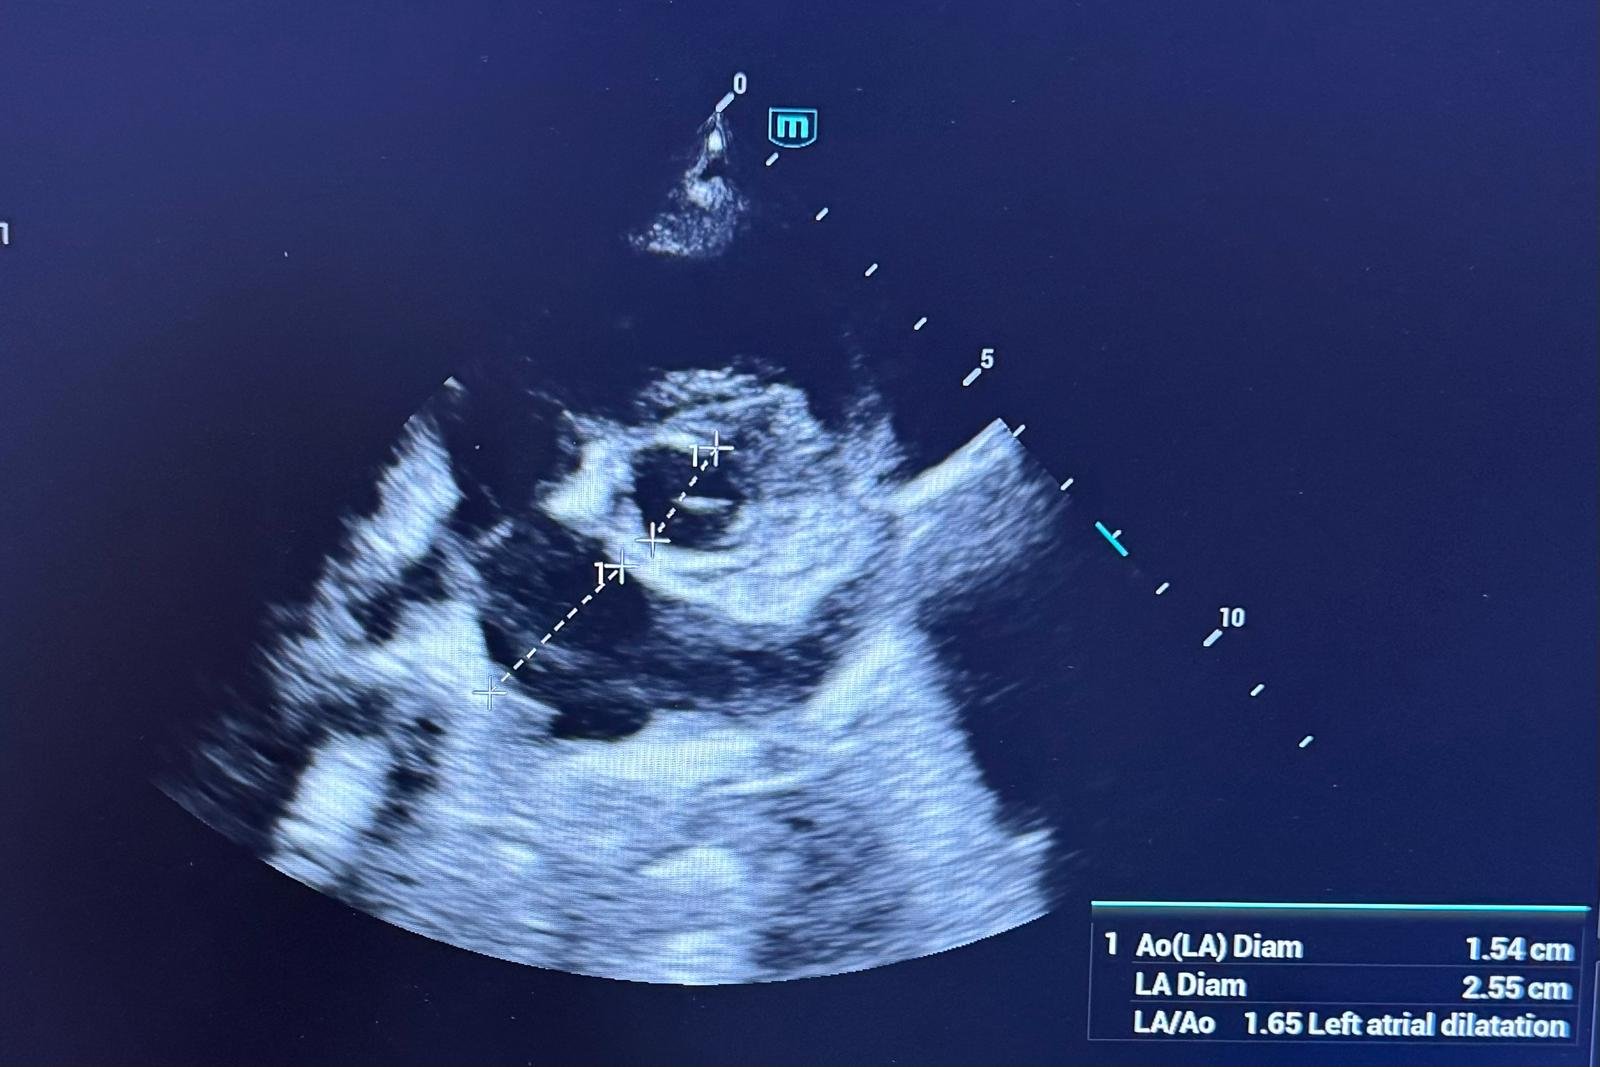

Ecocardiografia oferă informații detaliate despre structura și funcția inimii. Cu ajutorul unei ecocardiografii, care oferă informații detaliate despre structura și funcția inimii, medicul poate evalua dimensiunea camerelor cardiace, funcția valvelor și capacitatea de contracție a inimii. Această investigație ajută la depistarea bolilor cardiace înainte de apariția simptomelor severe.